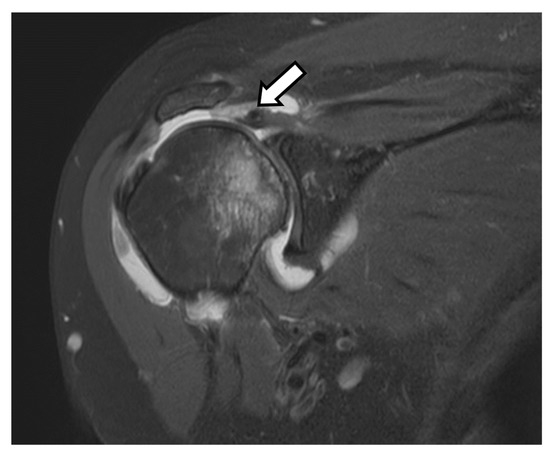

4.2.4. Rotator Cuff Tendon Tears

5.1.3. Anatomic Total Shoulder Arthroplasty (ATSA)